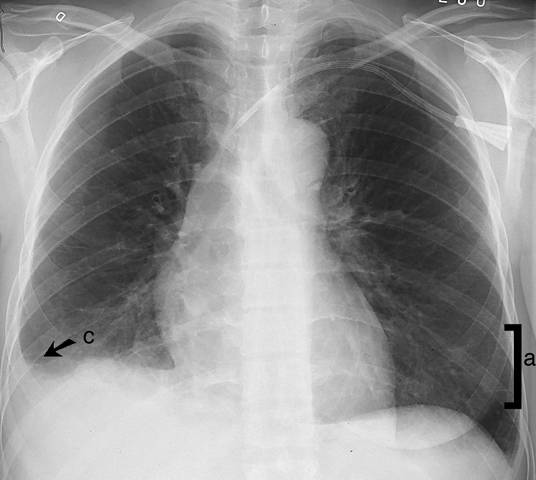

Kuva 1. Interstitiaalinen ödeema keuhkoissa (etukuva). Septaaliviivat (a) näkyvät parhaiten keuhkojen etukuvan ala-lateraaliosissa, pleuraa kohti kohtisuorina 1–2 cm:n mittaisina viivoina. Tilaan liittyy pleuraneste (c). Sivukuva: ks. «Interstitiaalinen ödeema keuhkoissa (sivukuva)»1.